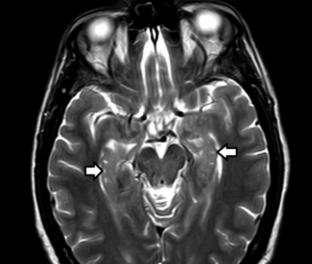

Se forman por defectos de fusión del asta de Amón con la circunvolución dentada durante la vida embrionaria.12,13 Se visualizan como una sucesión de imágenes quísticas en la circunvolución del hipocampo adoptando una configuración en "collar de perlas" (►Fig. 9).13 En imágenes presentan las características habituales de un quiste simple.12,13 Los diagnósticos diferenciales son12,13:

RM de cerebro, corte axial ponderado en T2; se muestran milimétricas imágenes de apariencia quística en las circunvoluciones hipocampales (flechas). Las mismas son remanentes del surco hipocampal.